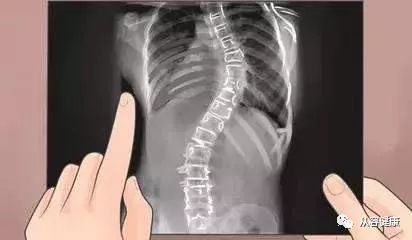

比如整脊调理,如果一个人脊柱有侧弯,用整脊手法调理过来,但是没有解决“筋”的问题,过几天脊柱又被与骨头紧密相连的“筋”给拉弯了,神经该被压迫的还是被压迫,没有解决根本问题。